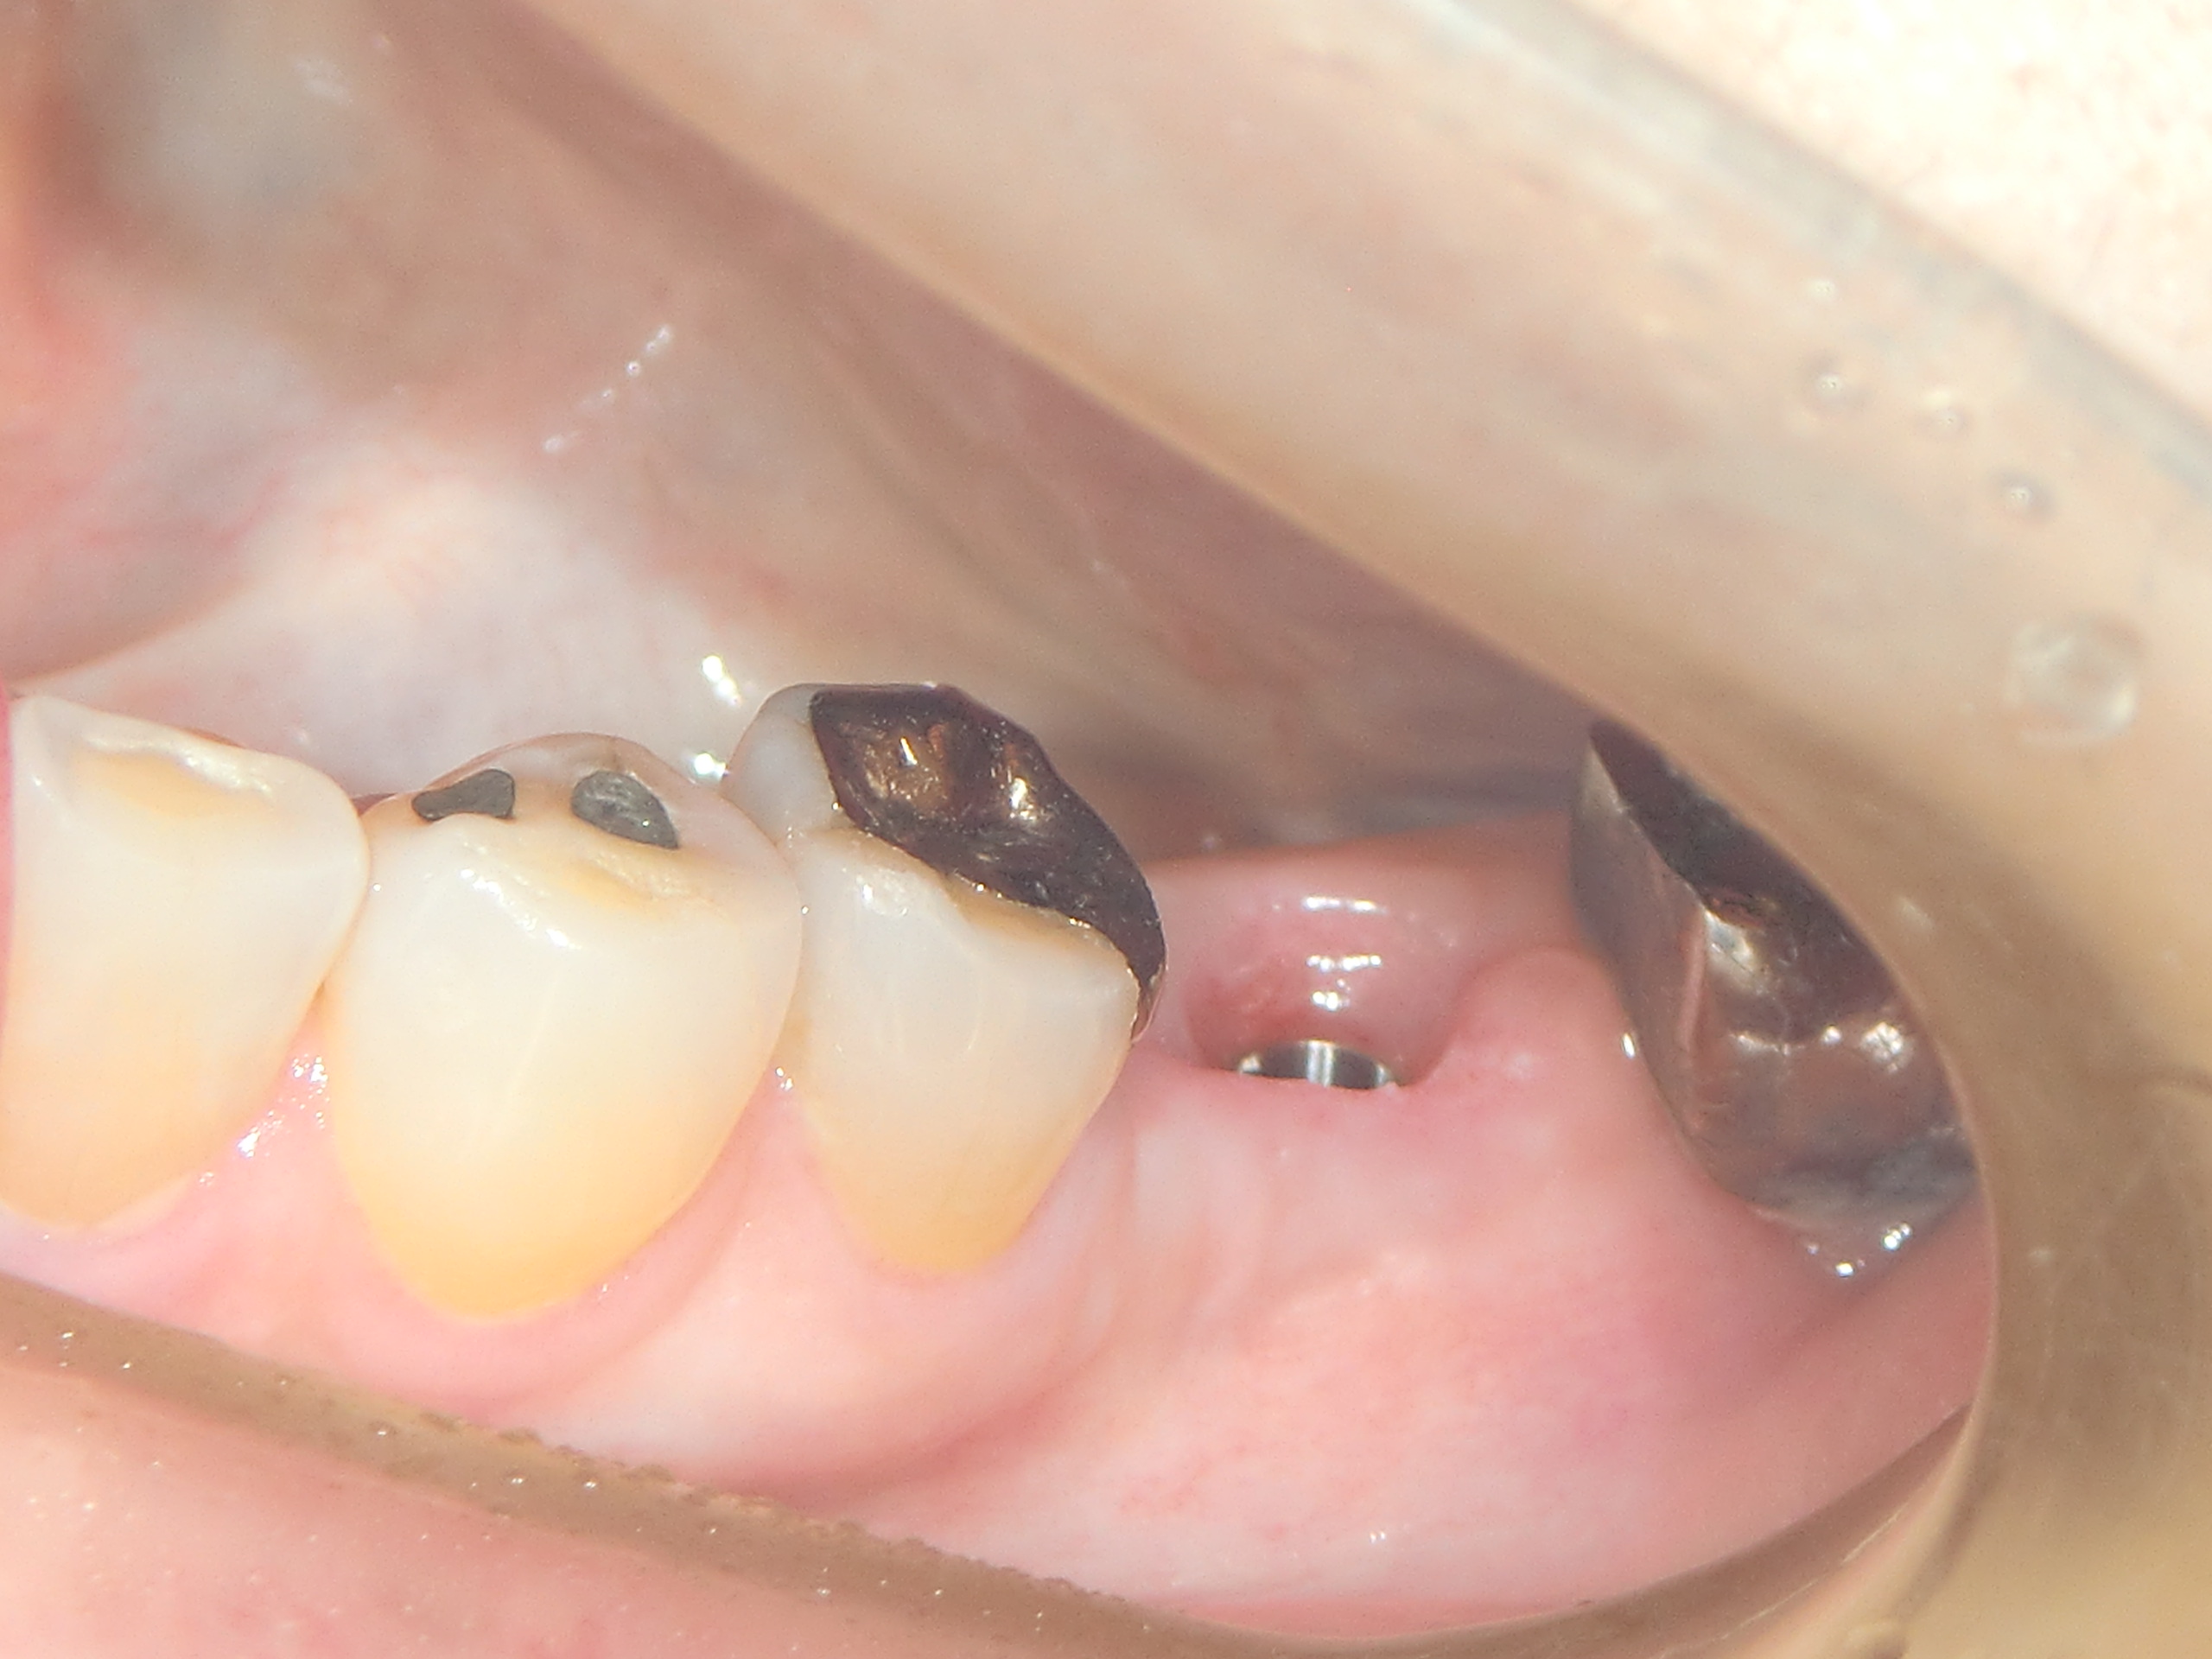

上2番目の歯をインプラント治療をしています(左から2本目) まだプロビジョナル(仮歯)です 最近プラスチックサージェリーという言葉を聞きませんか? 歯肉美容整形オペという意味です もともとプラスチックとは偽物とか仮のとかいう意味であまりよい意味では使いません。 われわれがおこなっているオース…